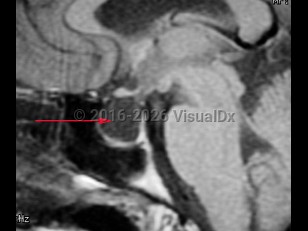

Empty sella syndrome

A syndrome characterized by flattening or regression of the pituitary gland within the sella turcica cavity, resulting in an MRI image of an empty sella turcica. This radiological finding may be associated with normal pituitary function. Less commonly, pituitary surgery or abnormal formation of the pituitary gland may lead to pituitary hypofunction.